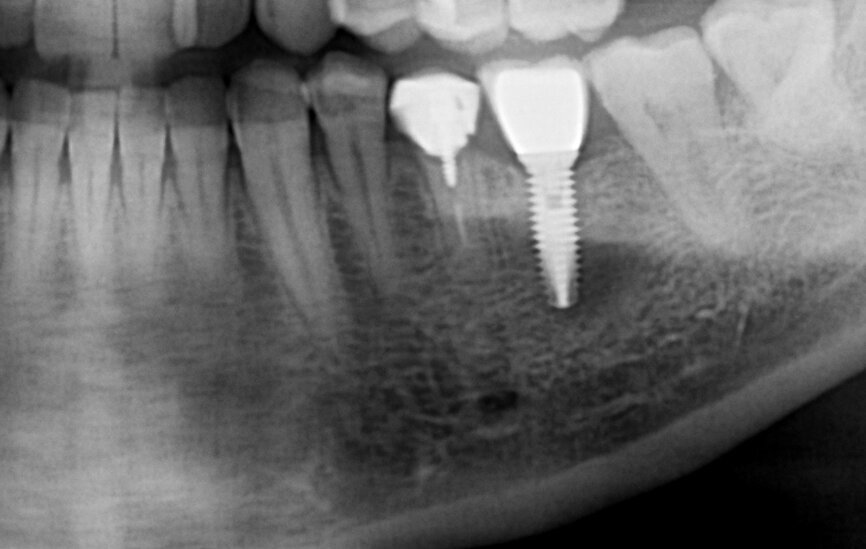

A healthy, non-smoking, 40-year-old male patient presented with a mandibular left first premolar with a fractured root. The root had previously been treated endodontically, three years before suffering a bone level transversal fracture (Figs.1a & b). The patient had already received several implants to replace some of his lost teeth over the previous nine years. The missing mandibular premolar could be easily seen and was one of his complaints. The patient had moderate aesthetic expectations, high functional demands and little time to come to the appointments.

Fig. 1a: Initial situation: apical radiograph (a), intra-oral view (b) and CT scan (c).

After analysing the computed tomography (CT) scan on BTI Scan II software (BTI Biotechnology Institute; Fig. 1c), the root was not considered to have the minimum criteria for retaining a crown, or a post and core and crown. As the bone availability, bone density and remaining buccal bone were considered to be ideal, implant therapy was immediately considered.

This CT scan was taken three years before the root fractured. As there was no infection related to the root and sulcus probing, all around the remaining root and all the way down to bone contact showed no socket alteration—a Type I socket was diagnosed—it was decided not to irradiate the patient further. This CT scan data, supported by the clinical examination, was considered reliable, despite the three years that had passed.